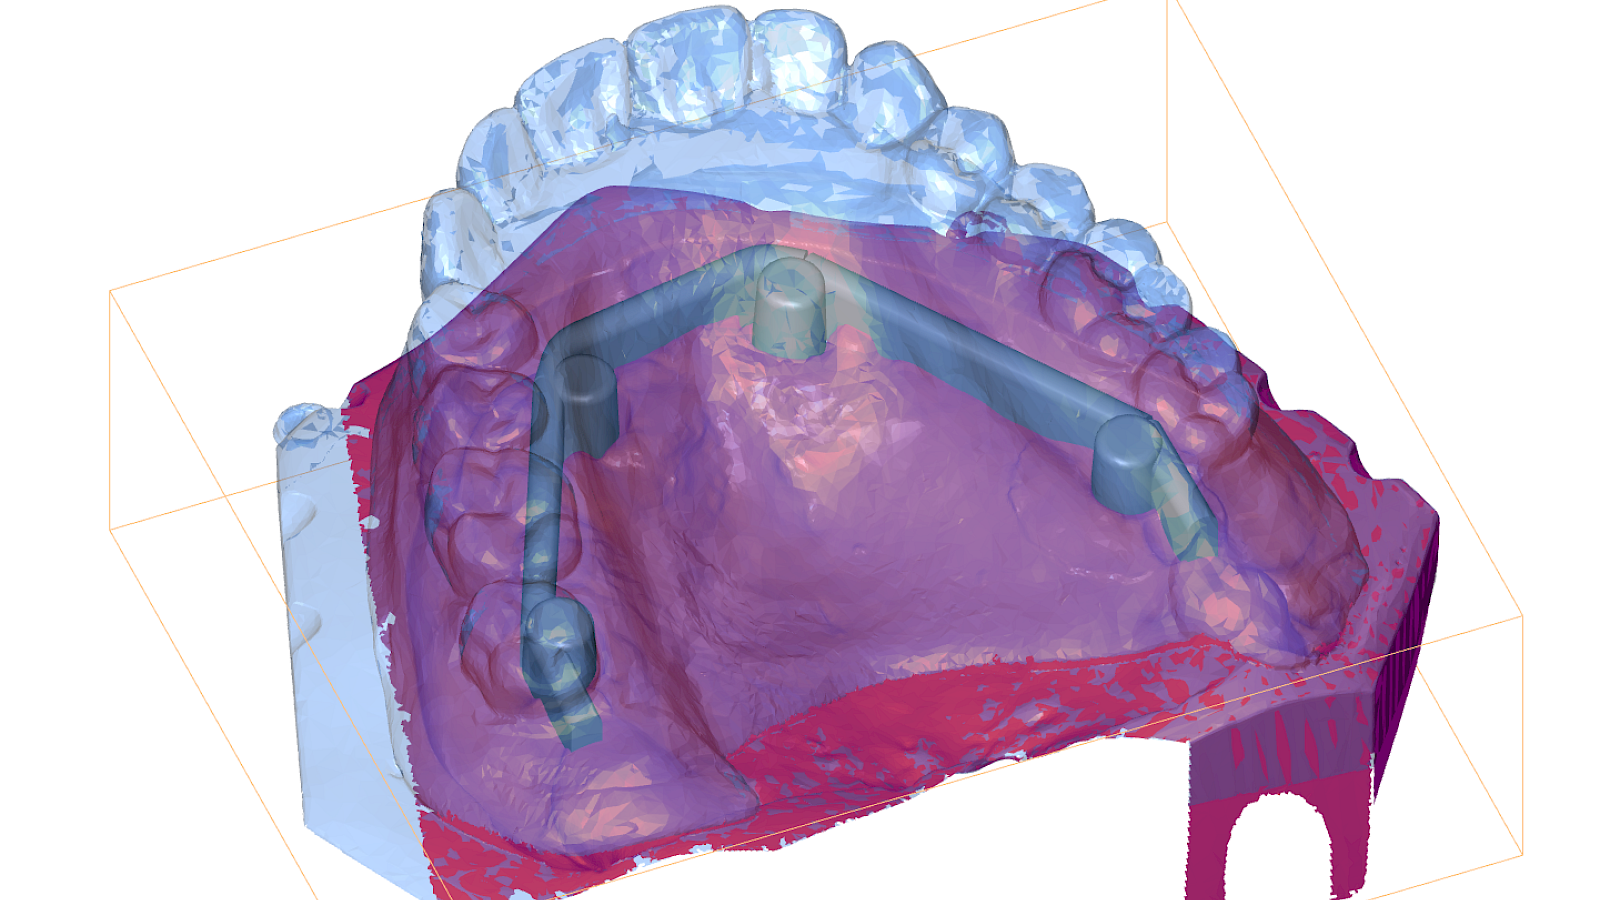

Participants will gain insights into contemporary treatment planning concepts, surgical approaches, and prosthodontic workflows. Digital tools such as virtual planning, guided surgery, and AI applications in implantology are highlighted throughout the course.

• Hands-on training for intraoral scanning, AI-based provisionals printing, model-based training implant placement and use of the Locator Fixed® system

6. Digital workflows & AI-based design

The curriculum features live surgeries, interactive lectures, and extensive hands-on training, including implant placement on models, impression-taking, and digital design exercises.